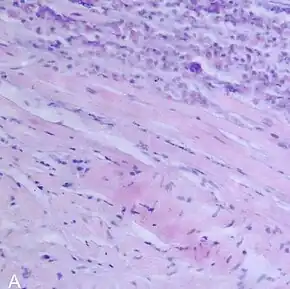

| A microscope image of myocarditis at autopsy in a person with acute onset of heart failure | |

The gold standard is the biopsy of the myocardium, in general done in the setting of angiography. A small tissue sample of the endocardium and myocardium is taken and investigated. The cause for the myocarditis can be only diagnosed by a biopsy. Endomyocardial biopsy samples are assessed for histopathology (how the tissue looks like under the microscope: myocardial interstitium may show abundant edema and inflammatory infiltrate, rich in lymphocytes and macrophages. Focal destruction of myocytes explains the myocardial pump failure.[11] In addition samples may be assessed with immunohistochemistry to determine which types of immune cells are involved in the reaction and how they are distributed. Furthermore, PCR and/or RT-PCR may be performed to identify particular viruses. Finally, further diagnostic methods like microRNA assays and gene-expression profile may be performed.